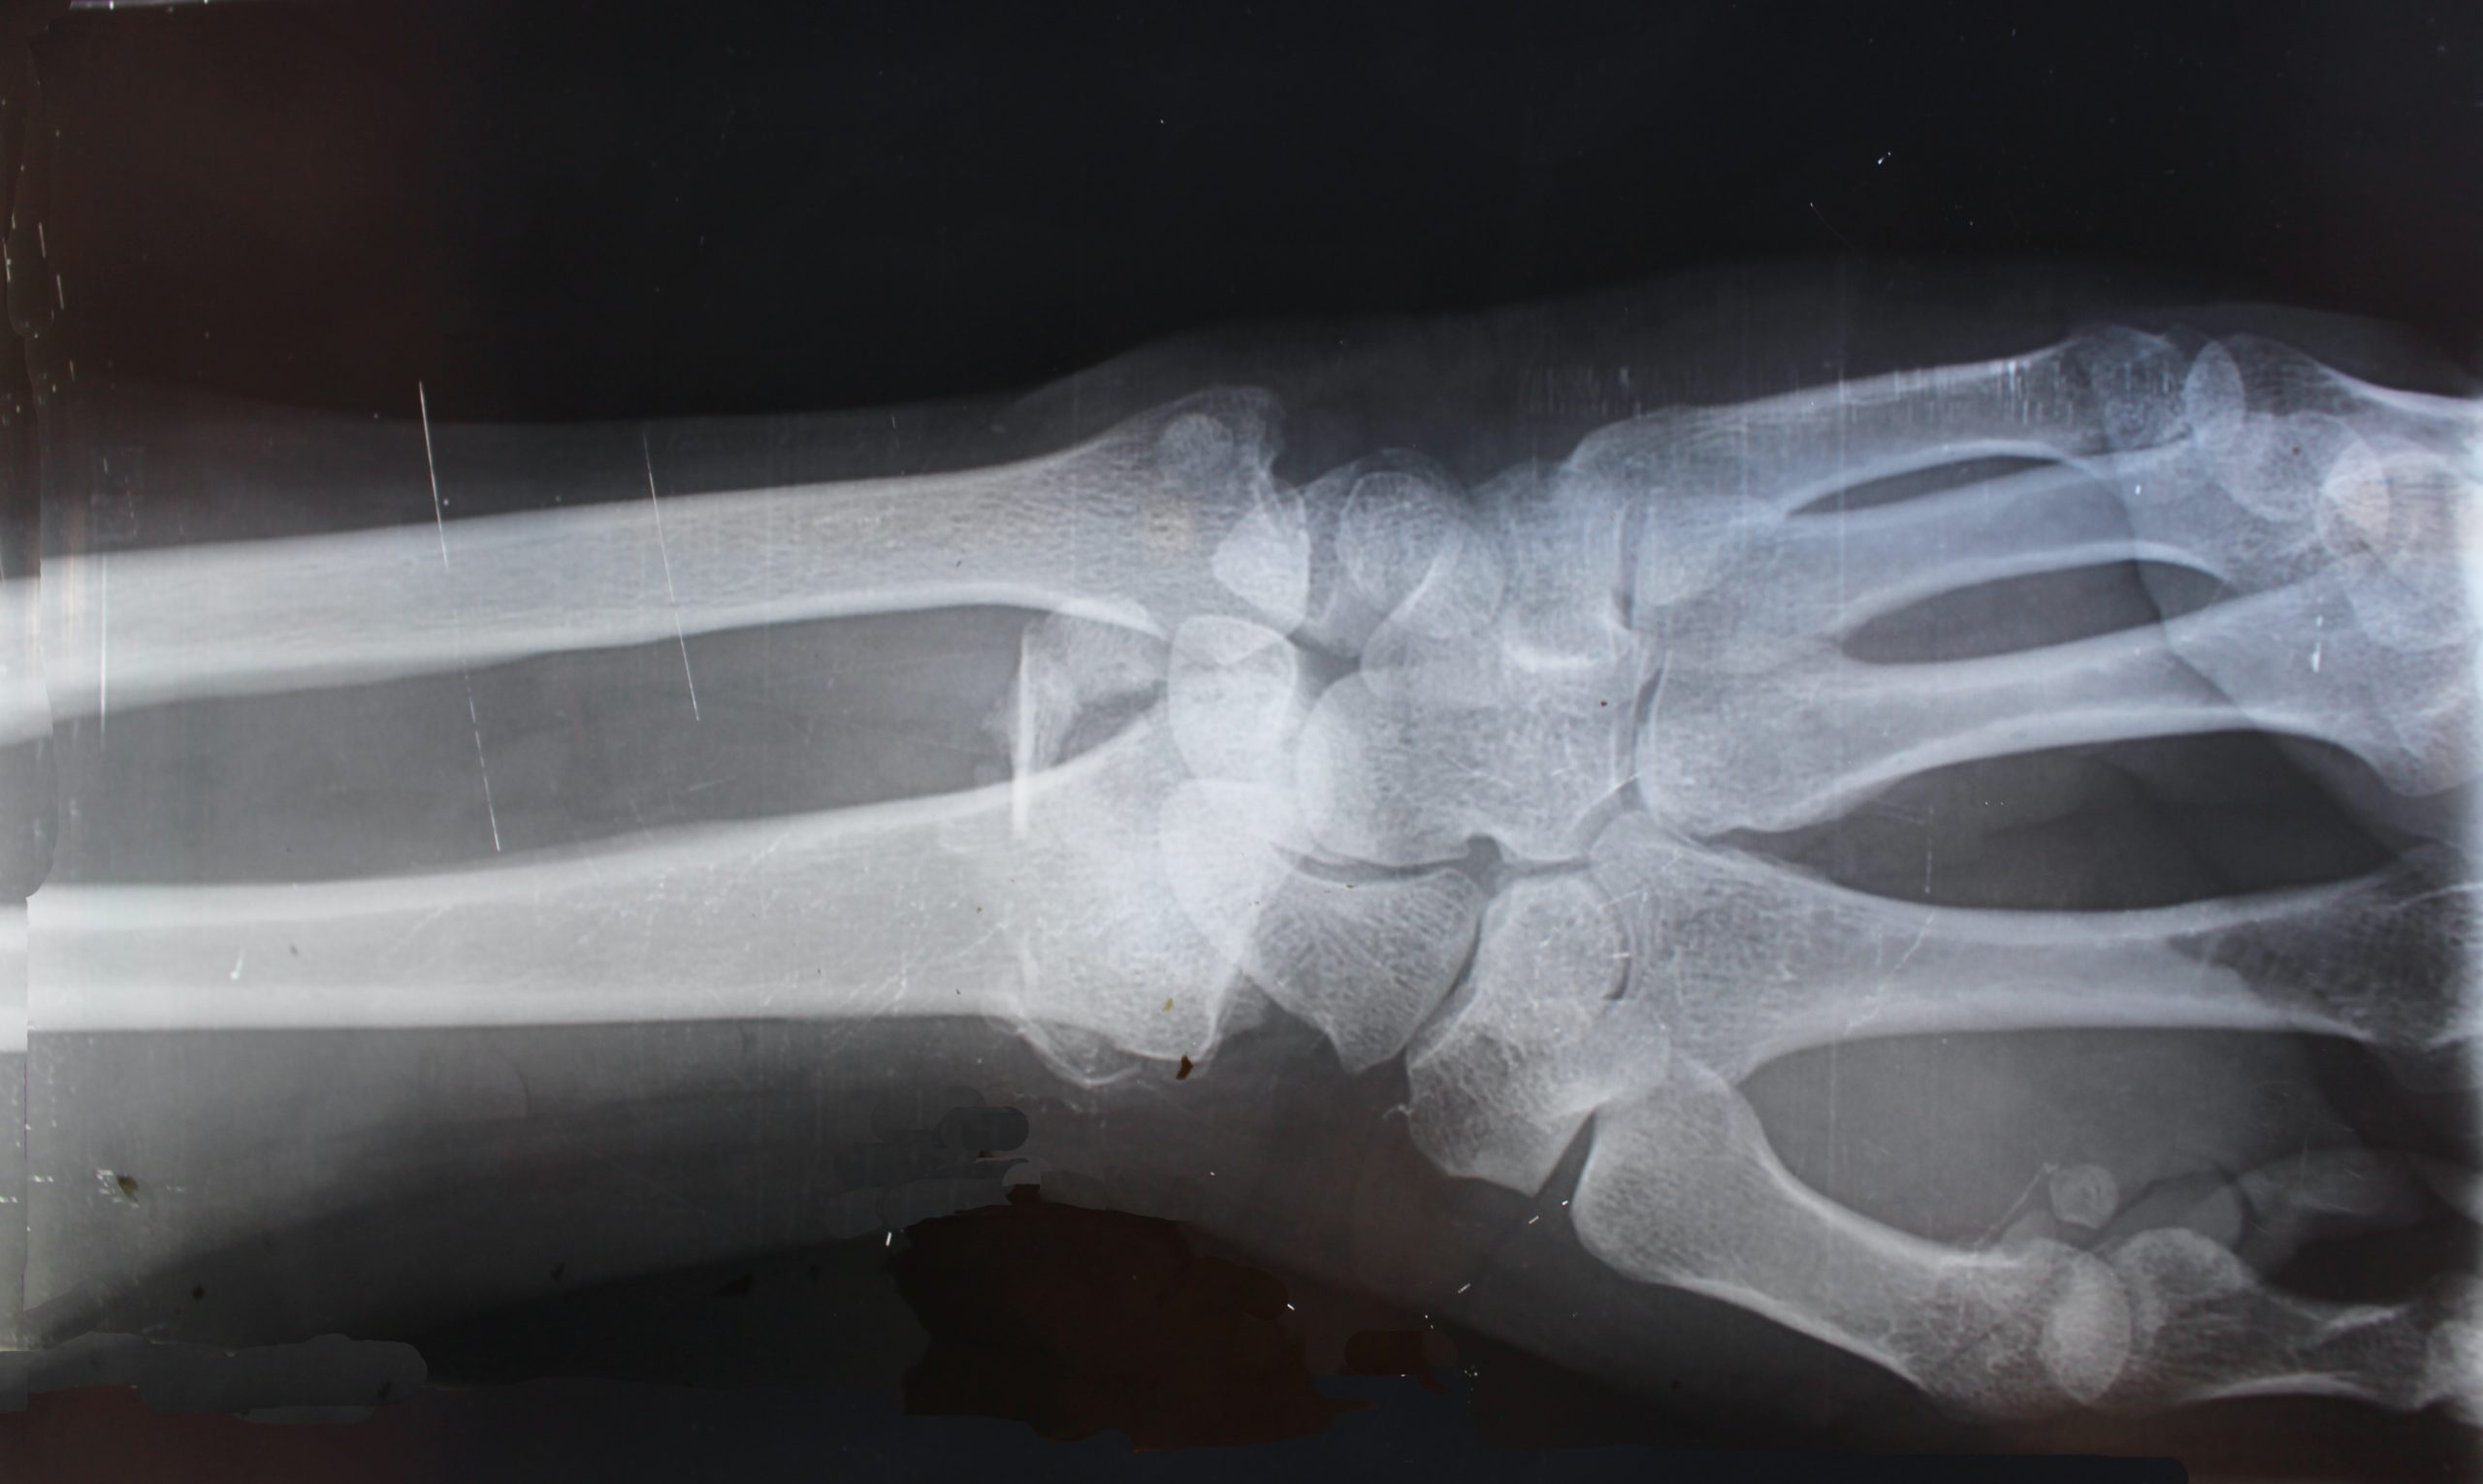

Analýza snímok z magnetickej rezonancie naznačila, že vírus môže spôsobiť to, že imunitný systém zaútočí na telo, čo vedie k dlhodobým reumatologickým komplikáciám. Výskum nadväzuje na predošlé správy týkajúce sa infikovanej Talianky, ktorej museli amputovať tri prsty. Spôsobené to bolo tým, že vírus jej zničil cievy.

Skoršie štúdie našli súvislosť medzi koronavírusom a bolesťami svalov a kĺbov. Tím z Northwest University použil viaceré zobrazovacie techniky od CT a magnetickej rezonancie až po ultrazvuk. Ich cieľom bolo odhaliť príčiny gangrény, ktoré sa začali objavovať u nakazených.

„Uvedomili sme si, že vírus COVID môže spôsobiť, že telo bude samo útočiť rôznymi spôsobmi. To môže viesť k reumatologickým problémom, ktoré si vyžadujú celoživotné liečenie,“ tvrdí doktor Swati Deshmukh, ktorý stál na čele výskumu.